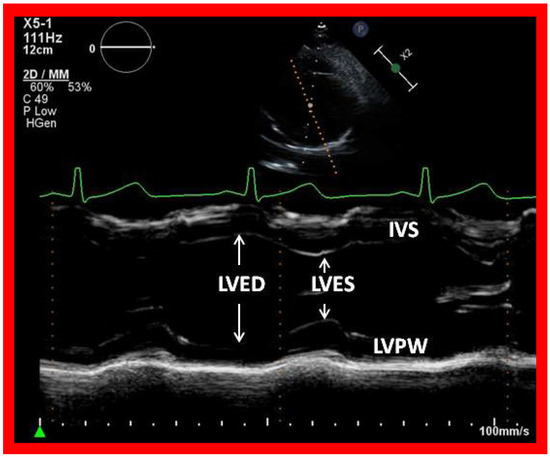

Figure 17. Selected video frame showing left ventricle in end diastole (LVED) and in end systole (LVES) demonstrating normal function. IVS, interventricular septum; LVPW, left ventricular posterior wall.

In most patients, LV size and function (Figure 17) remain within normal range, although large surgical shunts and inadequate PA banding may result in the deterioration of LV function. Consequently, periodic echo studies to monitor LV systolic function are recommended.